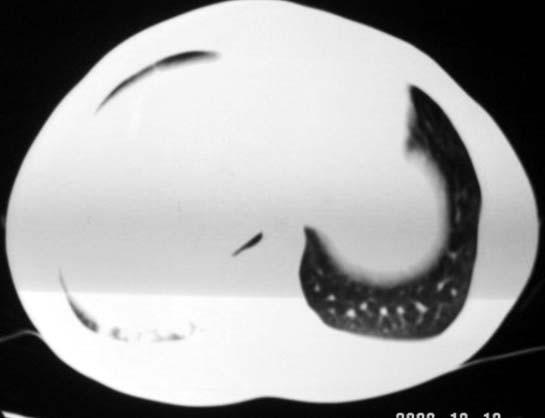

标题: CT5614:外伤病人男,20岁,右上腹痛.余肺野(-) [打印本页]

标题: CT5614:外伤病人男,20岁,右上腹痛.余肺野(-)

最后一幅图像病灶区可分椎旁肋骨骨折可能?请示骨窗,结合外伤史考虑右下肺挫伤。

最后一幅图像示椎旁肋骨走形欠自然,请示骨窗,结合外伤史考虑右下肺挫伤。

支持肋骨骨折,肺挫裂伤。